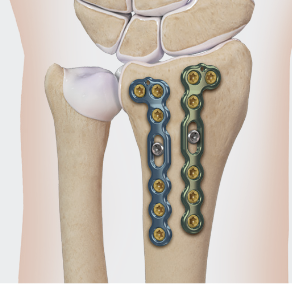

Dorsal distraction plating

Indication

Internal radiocarpal distraction

- unreconstructable distal radius fractures

- early weight bearing in poly trauma patients

- osteoporotic bone

Advantage - no pin site infection from external fixation

Disadvantage - need to remove plate at 3 - 4 months once fracture united

Technique

AO surgery foundation extended dorsal approach wrist

AO surgery foundation dorsal distraction plate

Arthrex dorsal spanning plate 2 incision video

Extended dorsal approach

- protect sensory radial nerve

- open 3rd extensor compartment / retract EPL radially

- mobilized 4th extensor compartment / retract EDC ulnarly

- bare area of radius proximally between EDC and ECRB / ECRL

Fixation to 2nd or 3rd metacarpal first

- 2nd metacarpal: under 2nd extensor compartment

- 3rd metacarpal: under 4th extensor compartment

- reduce / distract joint

- +/- additional radius fixation

Results

- systematic review of dorsal distraction plating

- 50% of wrist flexion extension compared to contralateral limb

- grip strength 80%